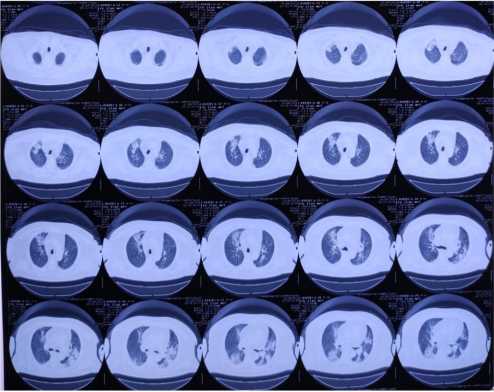

患者缘于12 d前无明显诱因出现发热,最高体温39.8℃,无明显规律;伴气短,活动后明显;伴乏力,偶有咳嗽、咳痰;无鼻塞、流涕,无咯血、盗汗,无心悸、胸痛等症状。于当地中医院给予静滴“头孢哌酮舒巴坦”抗感染及退热等治疗2 d,效果欠佳。为进一步治疗转入当地县医院,行胸部CT检查(2021-03-08)示:双肺多发片状模糊影(图1)。给予“头孢唑肟+环丙沙星”治疗7 d,其中联合“依替米星”治疗2 d。治疗过程中患者体温无明显下降,偶有咳嗽、咳痰,痰为白色黏液样,量少,伴全身乏力,气短症状进行性加重。为进一步诊治,转至我院急诊科抢救室,复查胸部CT(2021-03-16)示:双肺弥漫渗出影,双侧胸膜增厚(图2)。为进一步诊治,以“重症肺炎”收入呼吸监护室。患者自发病以来,精神、睡眠差,饮食差,大小便正常,体重无明显变化。

1  胸部CT可见双肺多发斑片状渗出实变影2021-03-08

2  胸部CT可见双肺弥漫渗出影,较前明显进展2021-03-16

经过上述综合救治措施6 d,患者氧合功能明显改善,呼吸机支持参数下调。自主呼吸试验成功后,顺利拔管脱机,序贯为经鼻高流量氧疗(HFNC),并停用卡泊芬净。复查胸部CT提示双肺渗出影较前吸收(图3)。2周时停更昔洛韦,复方磺胺甲噁唑维持治疗至3周。患者重症肌无力问题请神经内科会诊,建议继续予以溴吡斯的明60 mg 3次/d、甲泼尼龙20 mg/d的药物方案。后期加强康复训练,最终患者好转出院。

3  治疗前后胸部CT对比,胸部CT可见双肺渗出较前有所吸收2021-03-30)